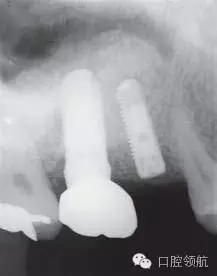

采取常規(guī)的上頜竇頰側(cè)壁開窗法,提升上頜竇黏膜,在( 左上第六顆牙)位置突入上頜竇內(nèi)的種植體表面的竇黏膜要非常小心地一點(diǎn)點(diǎn)剝離(圖4)。

圖4 采取側(cè)方入路提升上頜竇黏膜。毫無損傷地將覆蓋種植體表面的黏膜非常小心地一點(diǎn)點(diǎn)地剝離。

成功剝離后做鼻腔鼓氣實(shí)驗(yàn),確認(rèn)上頜竇黏膜是否穿孔,同時(shí)確認(rèn)( 左上第五顆牙)位置的上頜竇黏膜被剝離,在( 左上第五顆牙)位置植入種植體。同時(shí)逐漸向上頜竇內(nèi)植入植骨材料,避免( 左上第六顆牙) 植體表面周圍形成死腔(圖5~圖7)。

圖5 在( 左上第六顆牙)位置的種植體近遠(yuǎn)中逐漸向上頜竇內(nèi)側(cè)植入植骨材料,一定注意不要形成死腔。